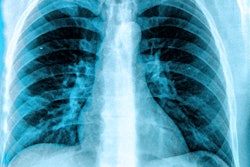

KA Imaging is touting early trial results that show the company's Reveal 35C system with a portable dual-energy subtraction x-ray detector detects more pneumonia cases than traditional x-ray units.

The Reveal 35C technology was shown to detect 25% more pneumonia cases, including COVID-19, than traditional x-rays, according to a paper that was presented at the European Congress of Radiology (ECR) 2021. The trial is ongoing in Toronto, according to the company.